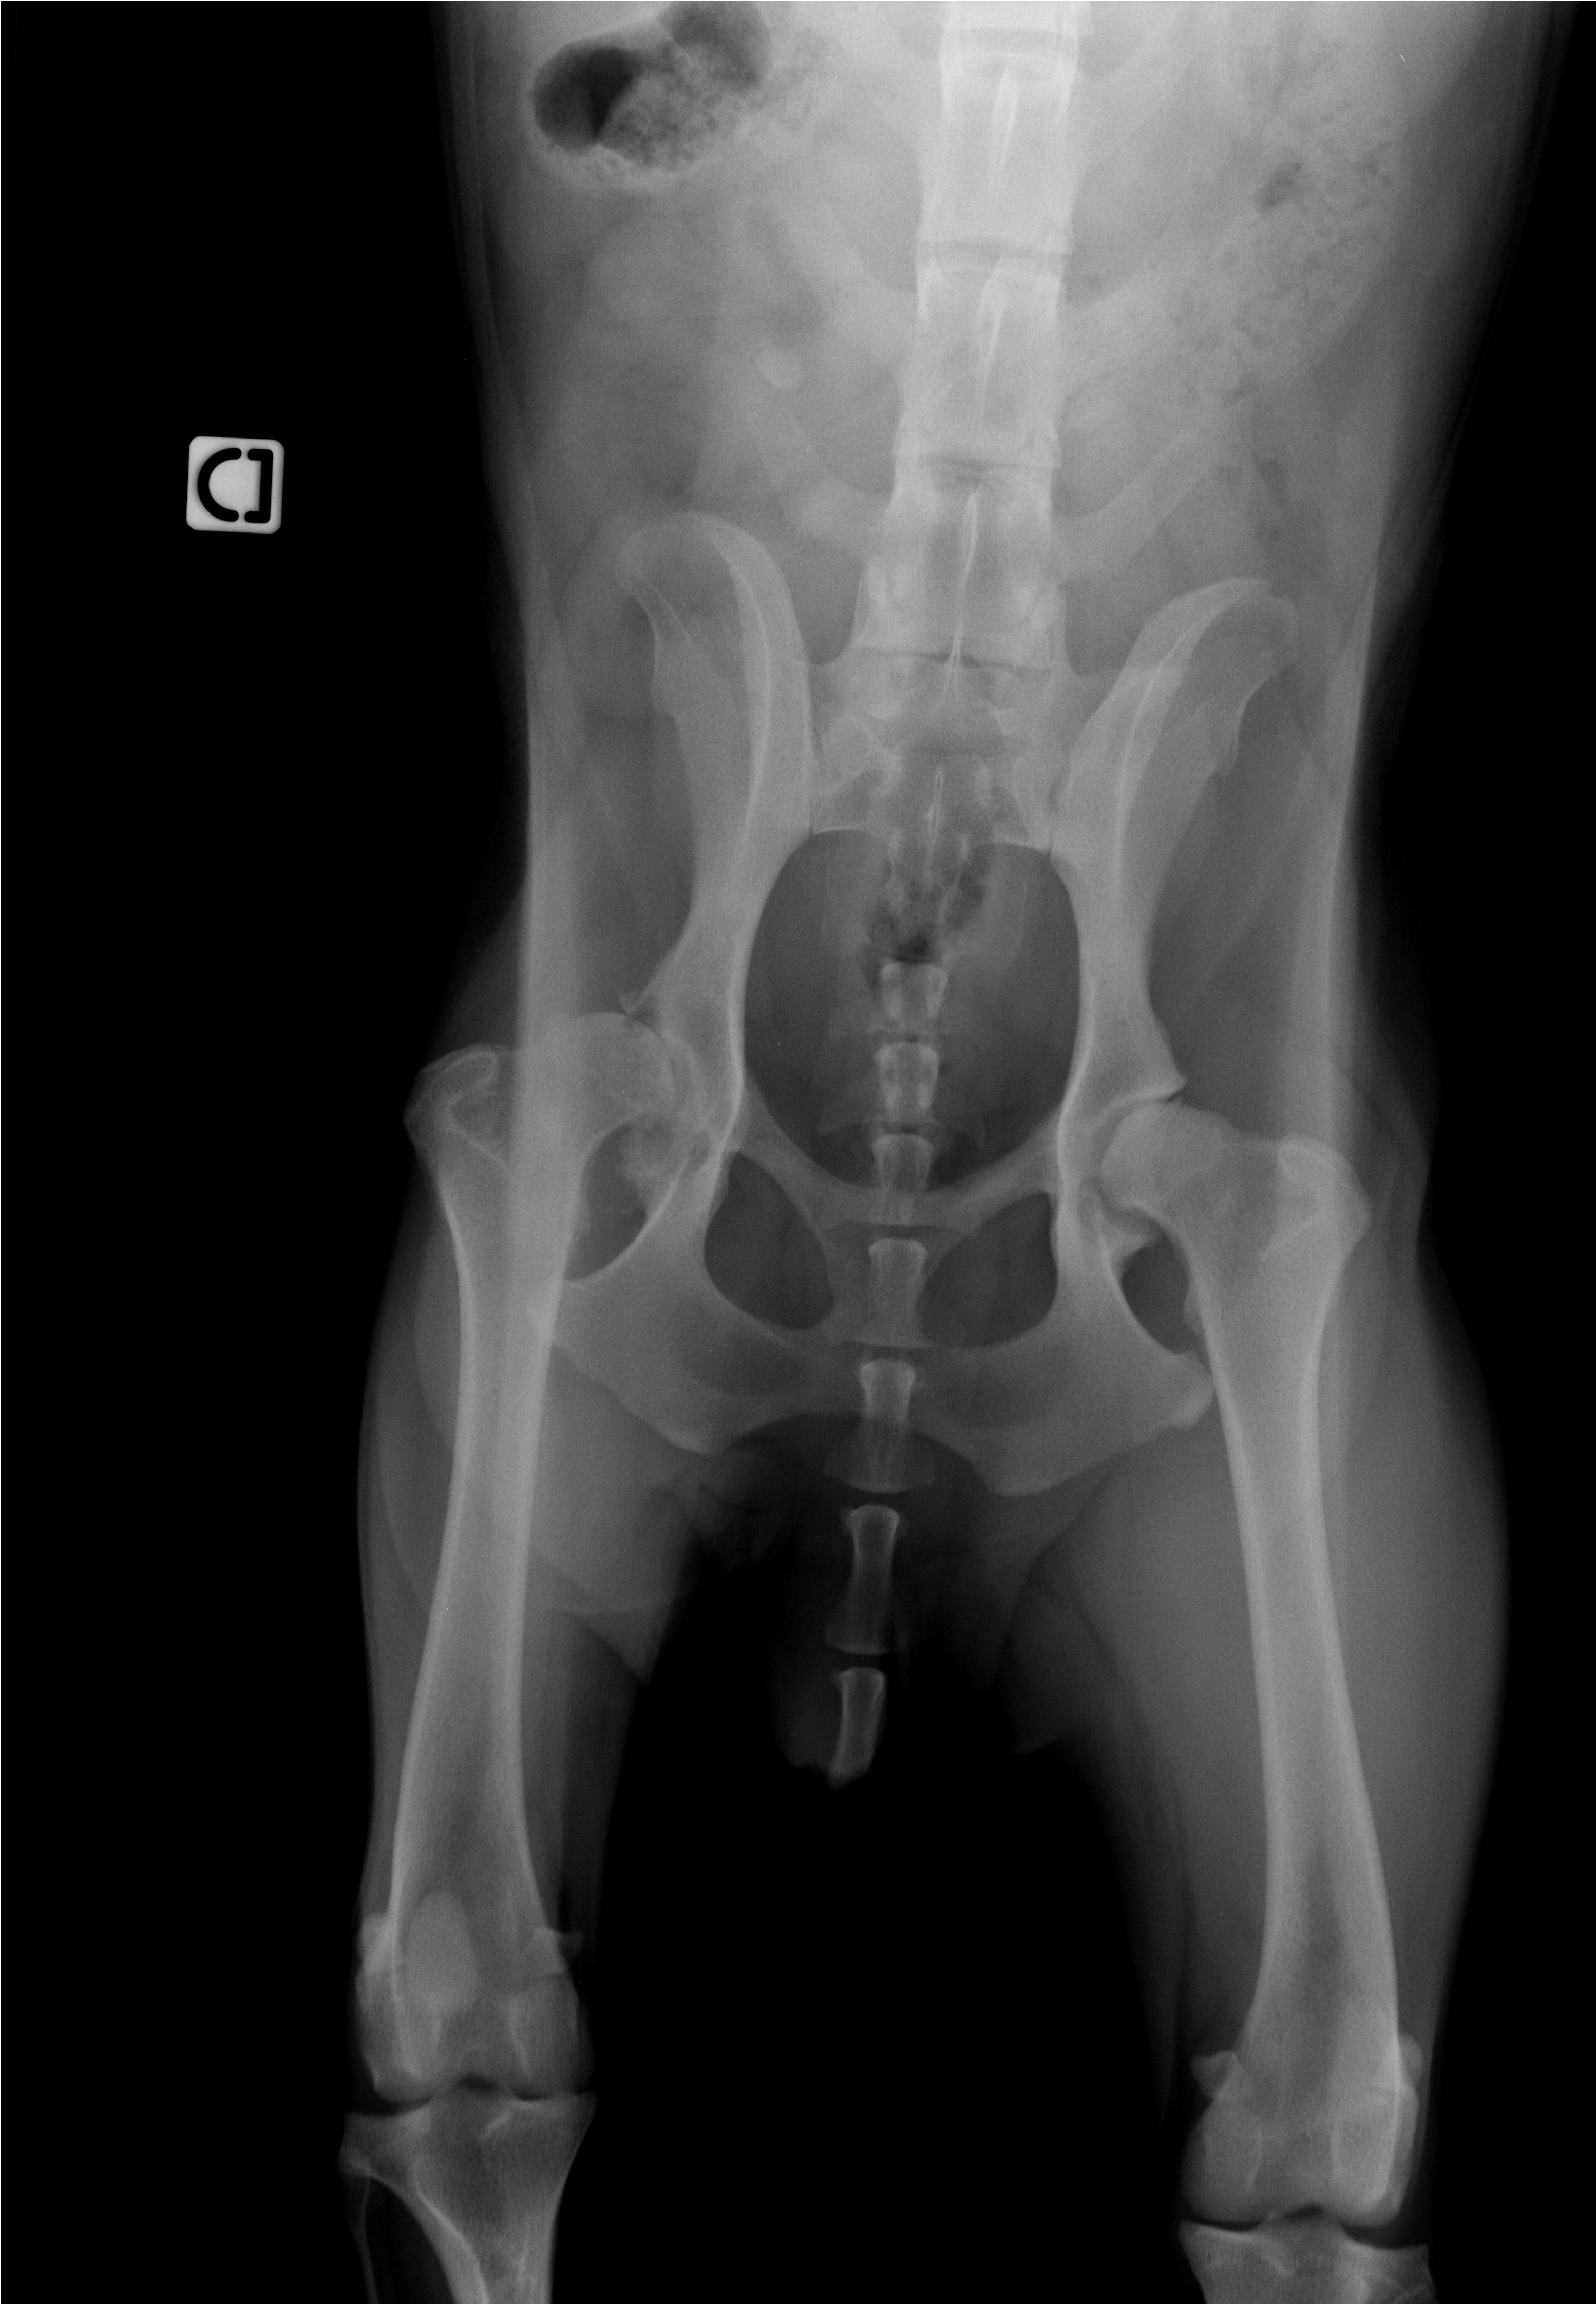

Donc il y a plus de trois semaines Hyole s'est remise à boiter fortement du jour au lendemain sans aucun signe avant. 20 jours d'anti inflammatoires et aucune amélioration , radios et le verdict tombe , la tete du fémur se désagrège comme la hanche et le cartilage n'existe plus .

La fonte musculaire est totale .

Les radios Dysplasie fin d'alphabet